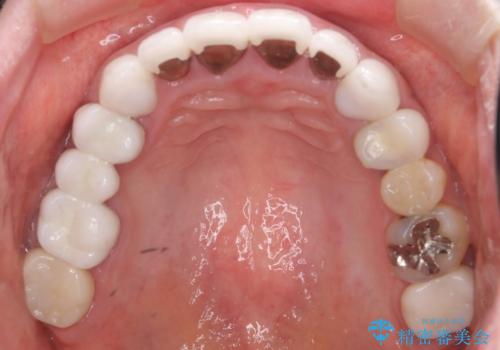

患者様のご希望により、金属を使わないオールセラミックのブリッジによる補綴治療を行いました。

金属の土台も除去し、ファイバーコア(金属を使わない強度のあるしなやかな土台)へやりかえました。

クラウンの種類:オールセラミッククラウン スタンダード